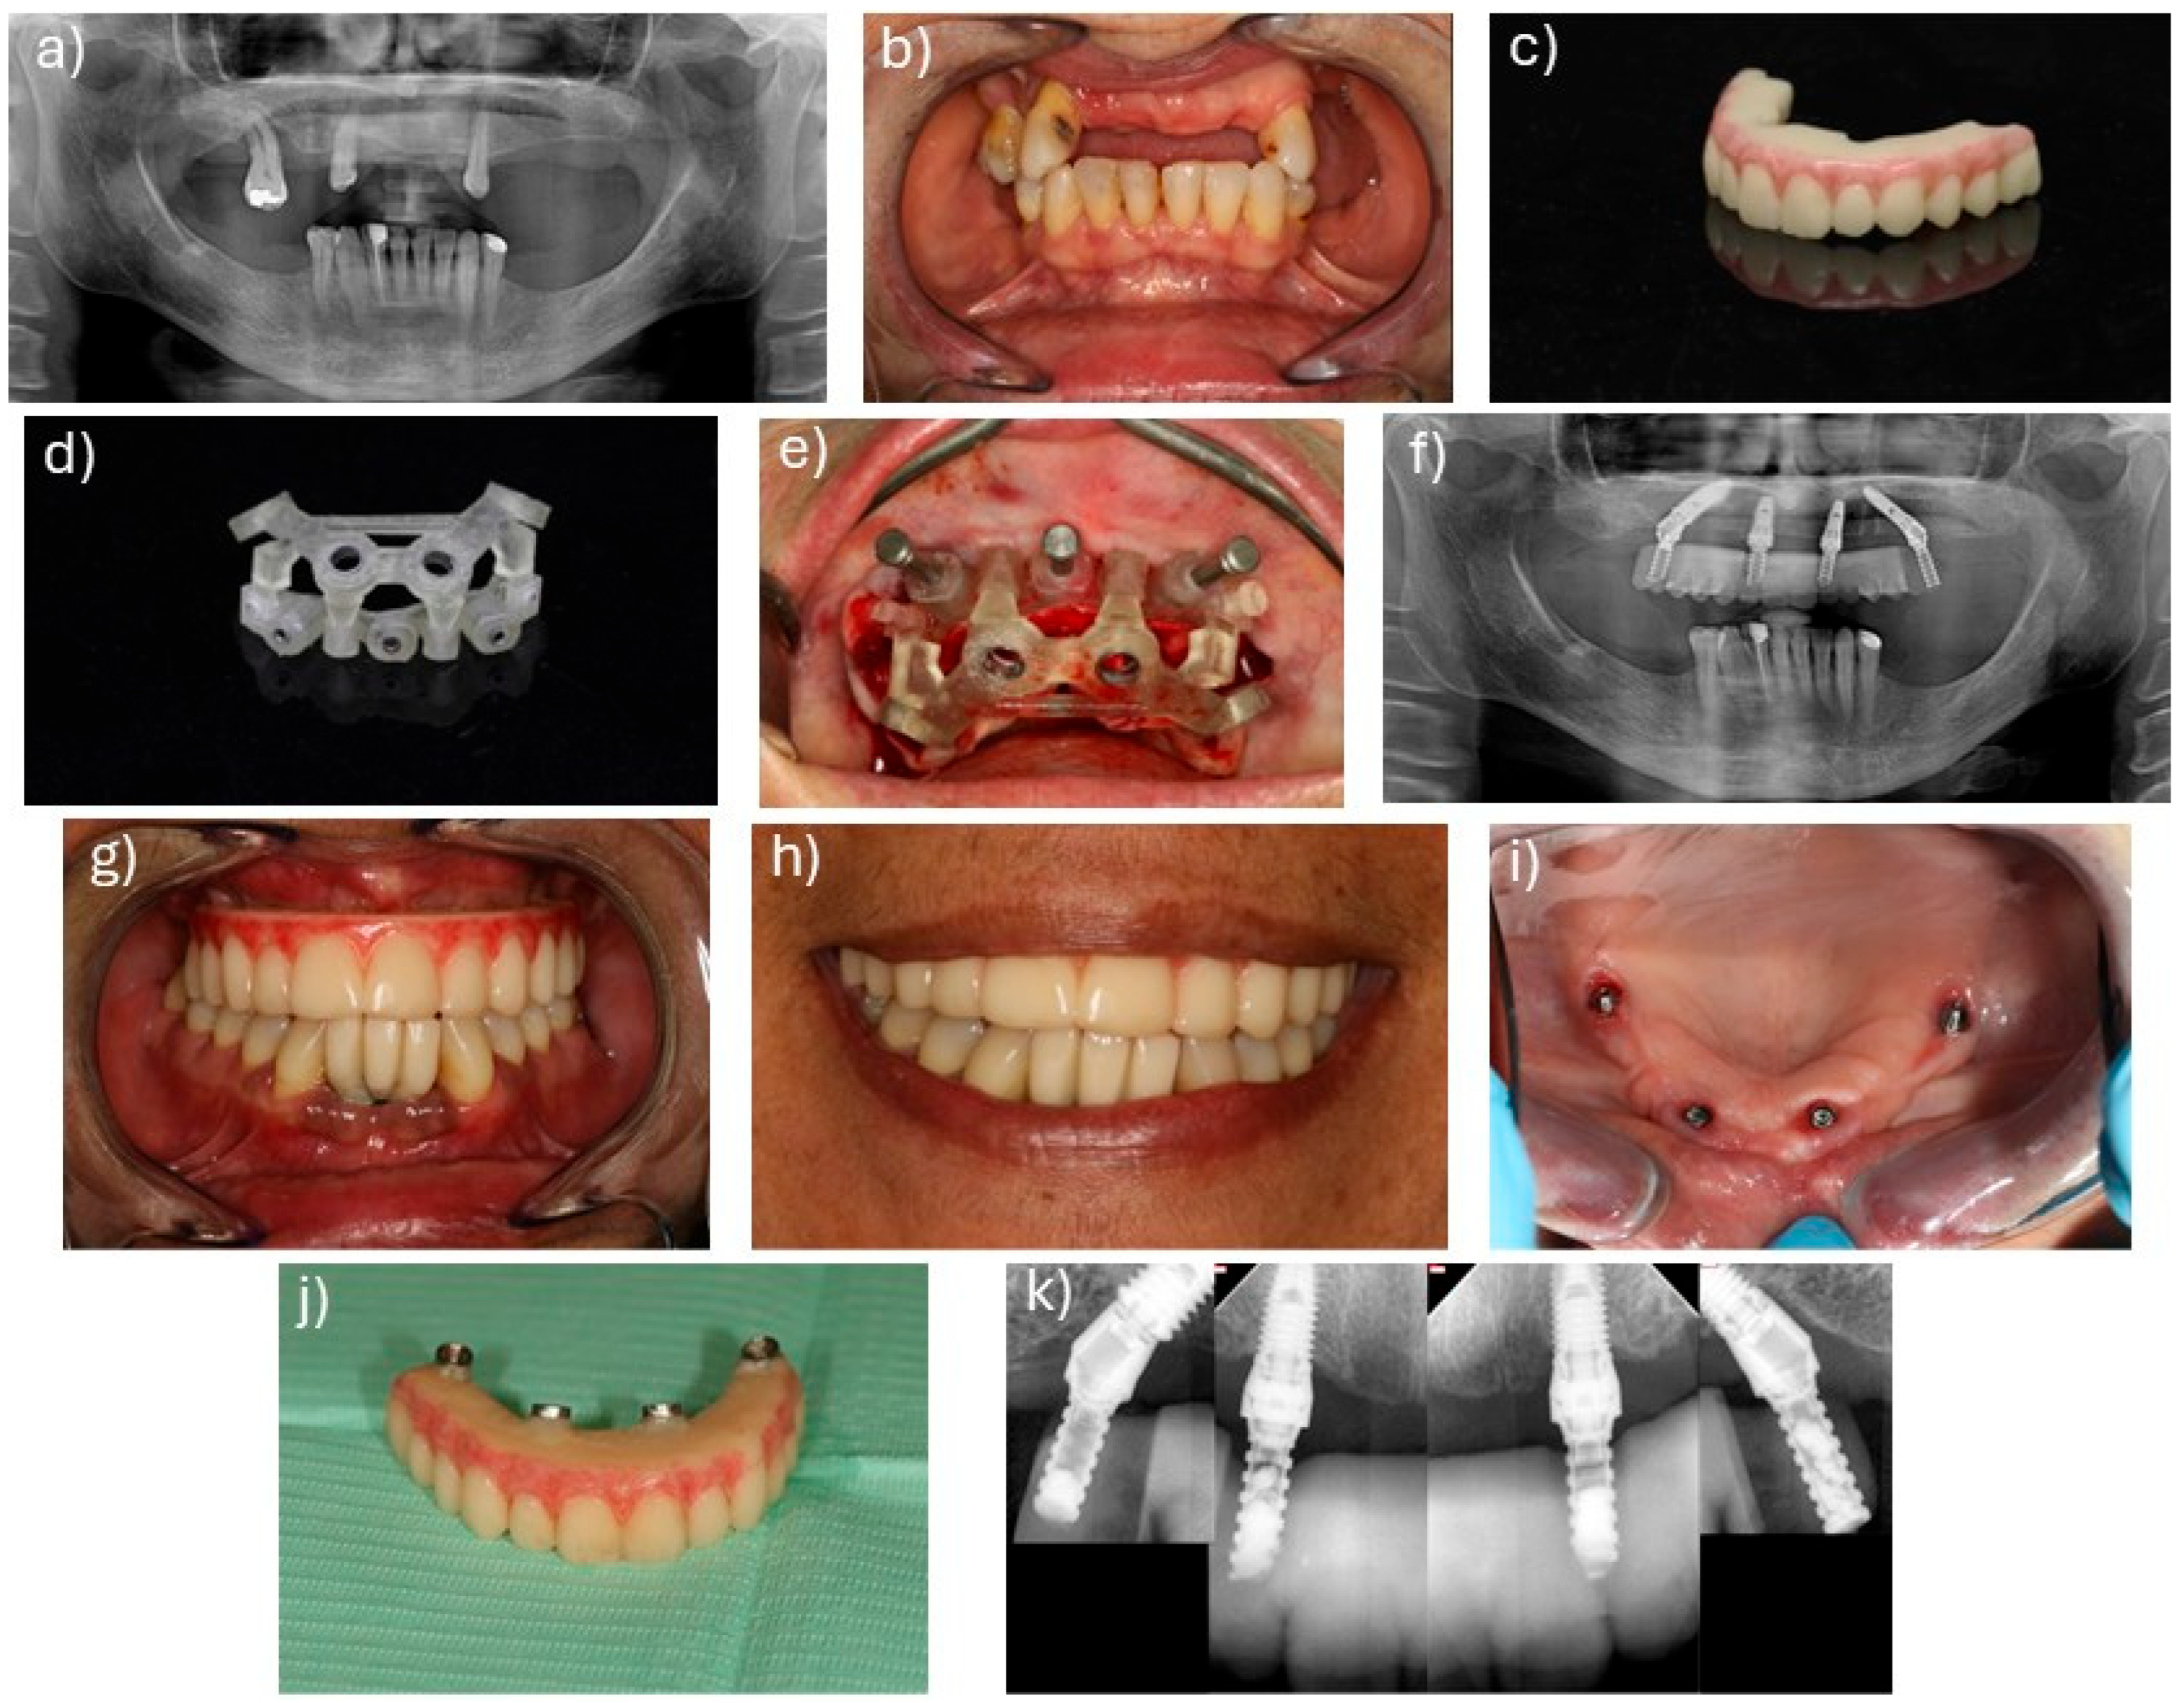

2.2. Surgical and Prosthetic Protocols